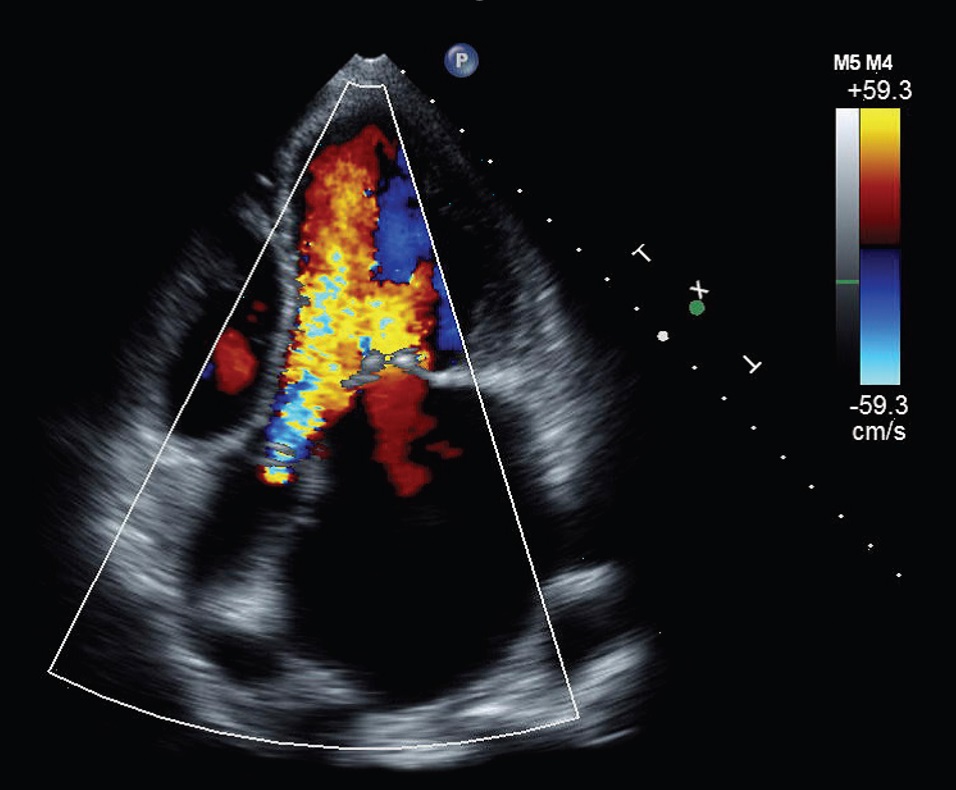

Hình ảnh trong buồng tim trên siêu âm Doppler màu

Trong quá trình làm siêu âm tim, bác sỹ sẽ dùng một hoặc một số đầu dò thích hợp để soi vào tim qua thành ngực hoặc từ vị trí khác để

lấy hình ảnh của tim thông qua sóng siêu âm.